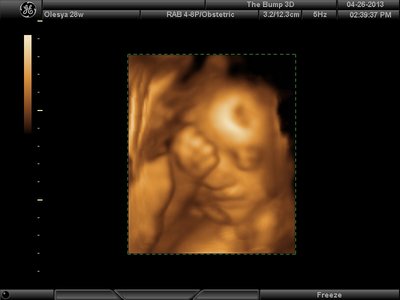

Вот, наш губошлёп:)

FACE.png [ 91.95 КБ | Просмотров: 1241 ]

Ой, Ксюнь, класс!!! Я говорю у вас у всех очертания носика, губок видны отлично...у моей же все размыто как-то и везде разное. На одной фотке вообще не нос а аэродром. Я ничего не поняла. Но УЗИстка сказала что она очень близко к плаценте мордашкой была поэтому так мутно все. Я надеюсь они мне переделают бесплатно все же. Я бы очень хотела. Так рассмотреть охото как следует, за это ведь и платила как никак..:-)